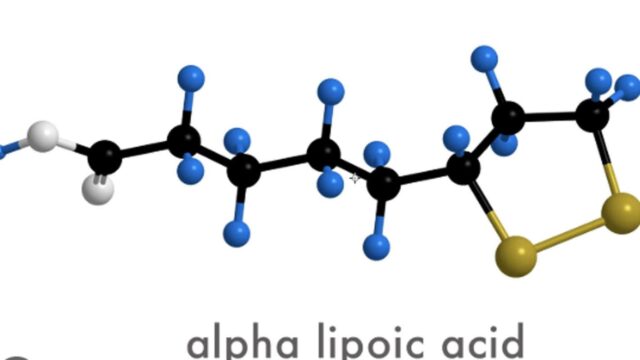

알파리포산 ALA 효과 효능 우리 몸에 작용하는 역할 장점 단점 부작용 주의사항 등 다방면으로의 정보